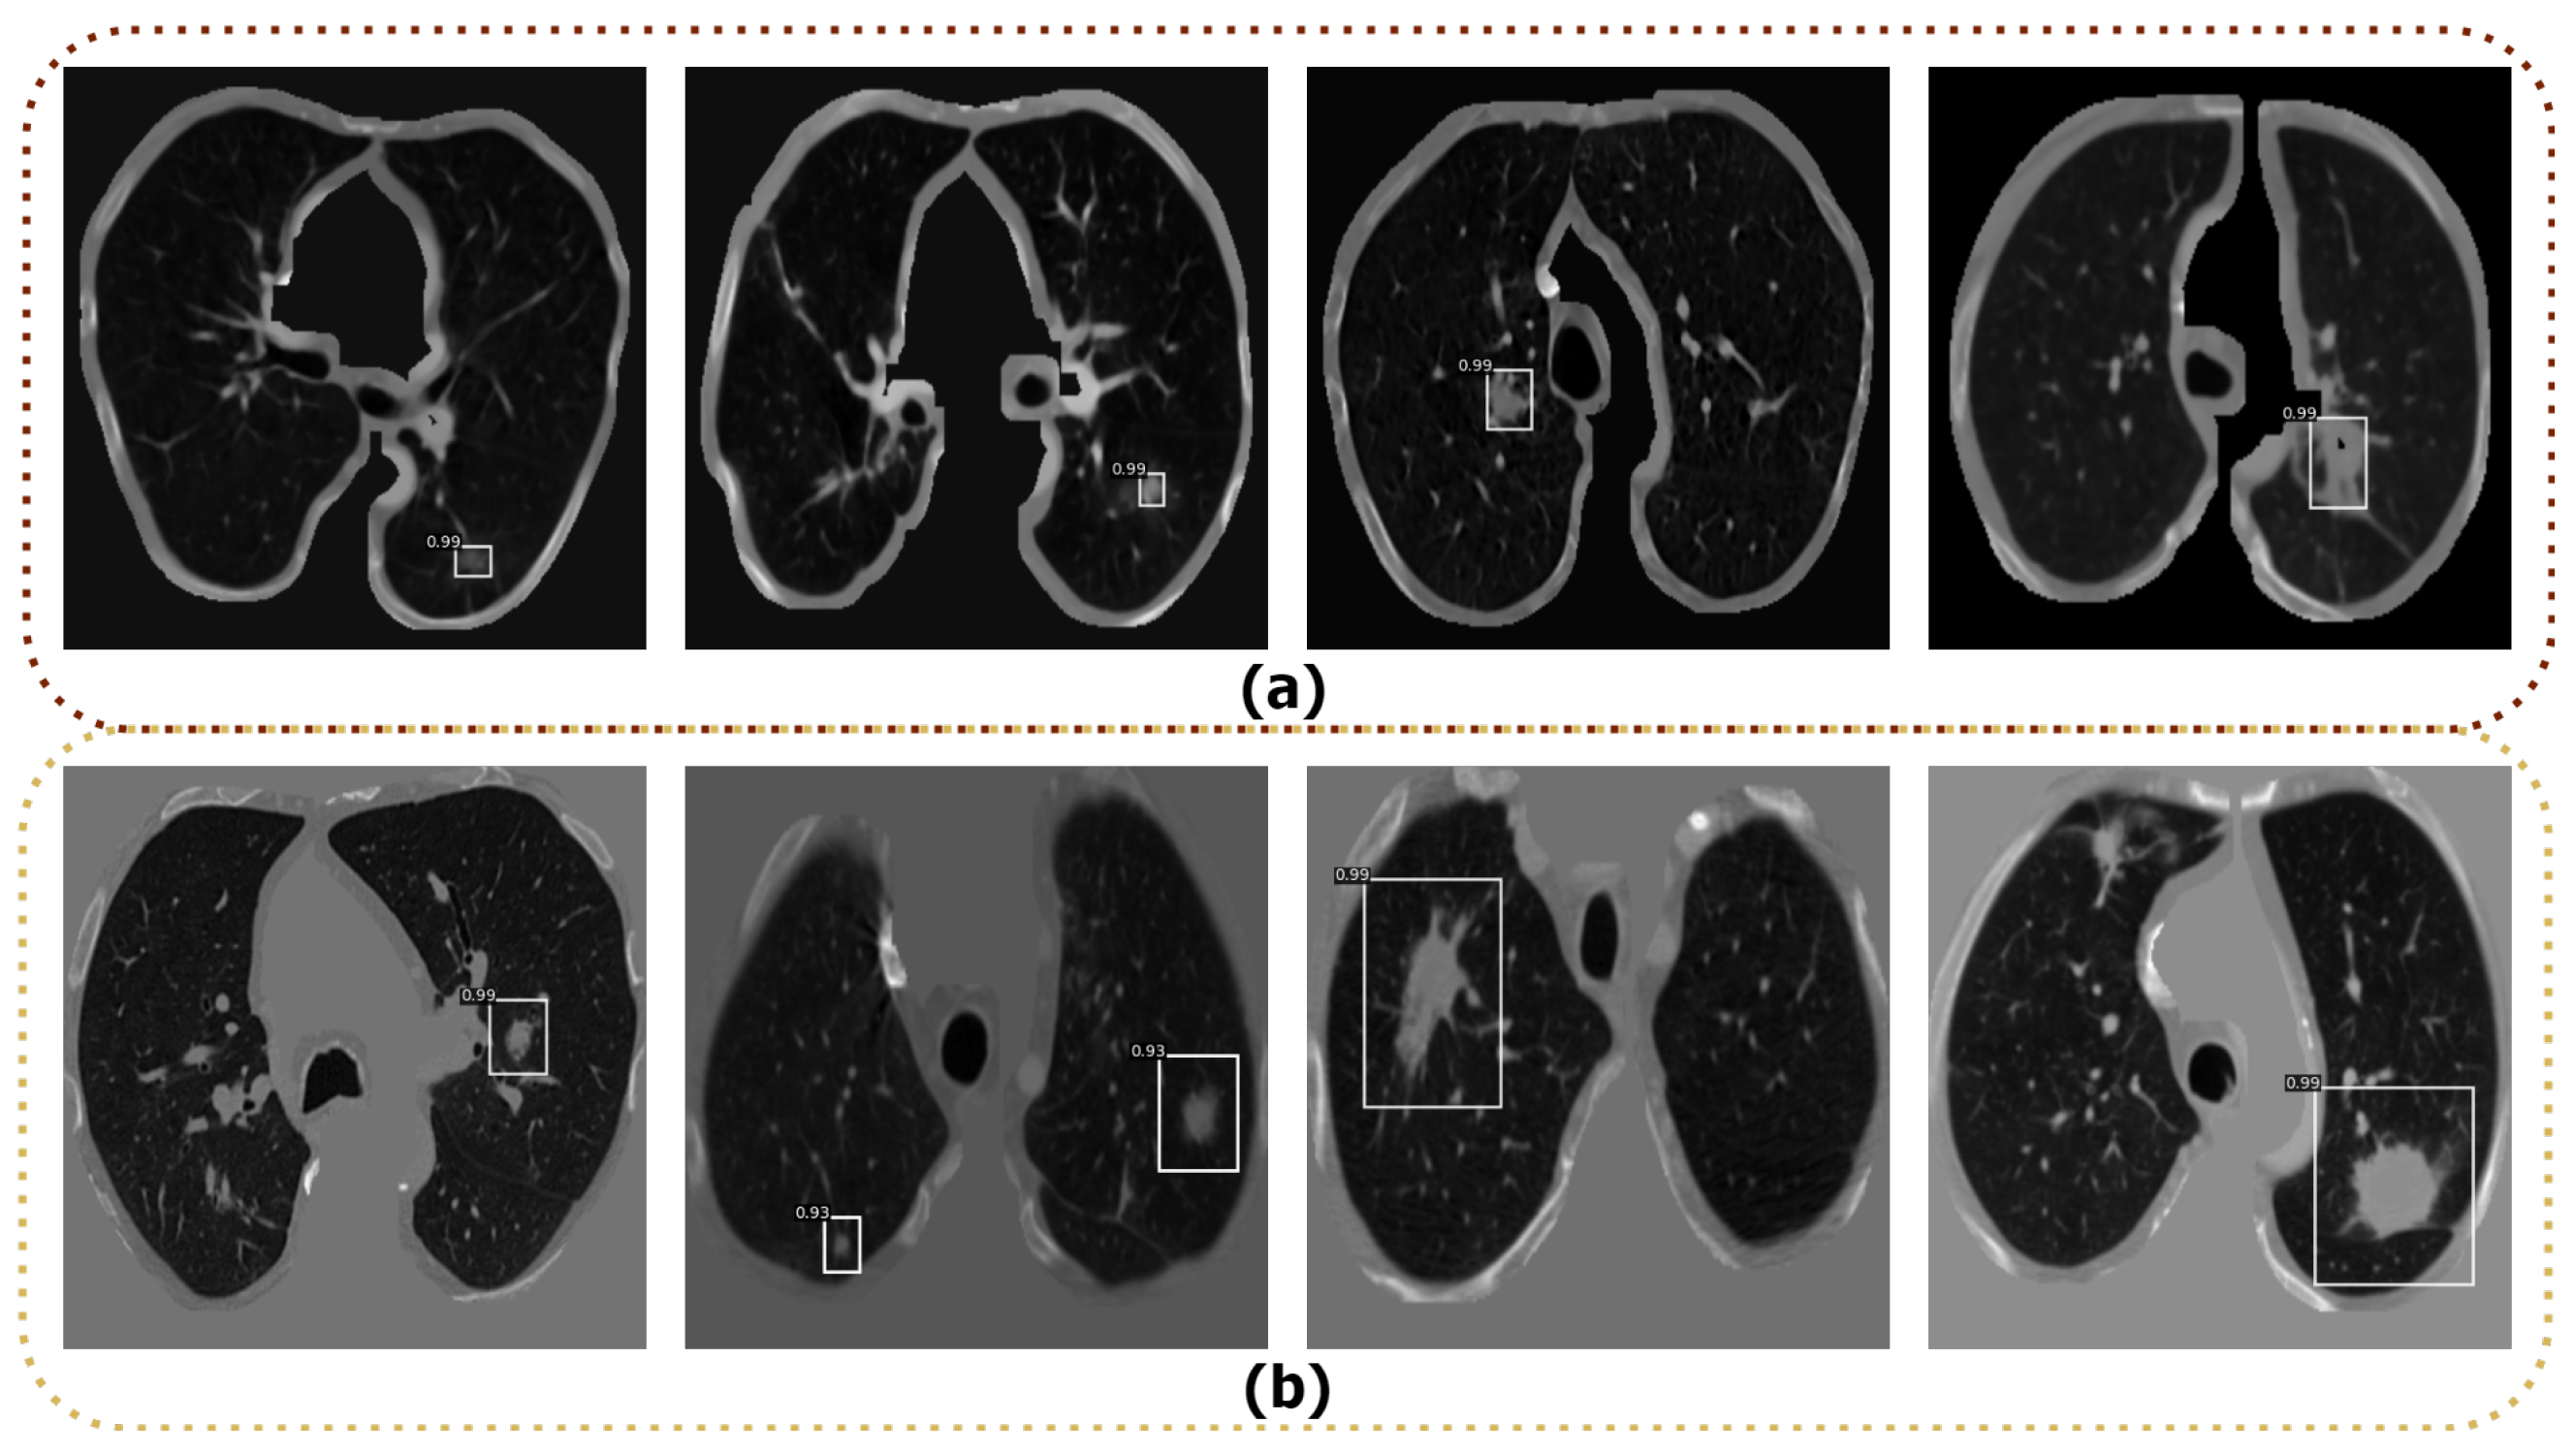

4.4. Nodule Detection

4.5. Nodule Segmentation